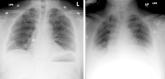

Fishing for a Diagnosis